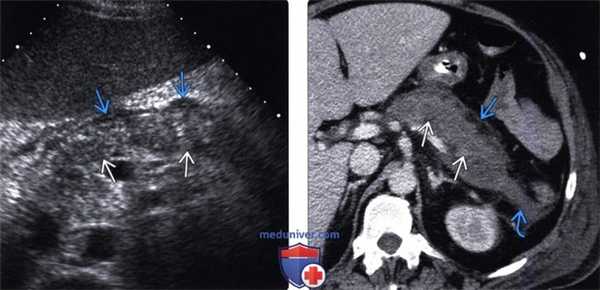

(Левый) На поперечном УЗ срезе брюшной полости визуализируется гетерогенная гипоэхогенная поджелудочная железа, что соответствует картине интерстициального отечного панкреатита. Спереди от тела поджелудочной железы определяется ги-поэхогенная перипанкреатическая жидкость, соответствующая острому скоплению секрета поджелудочной железы.

(Правый) У этого же пациента при КТ с контрастным усилением визуализируется гетерогенная низкоконтрастная поджелудочная железа, что соответствует картине интерстициального отечного панкреатита. Тело поджелудочной железы окружено зоной перипанкреатического отека; кроме того, в области хвоста железы определяется скопление секрета поджелудочной железы.